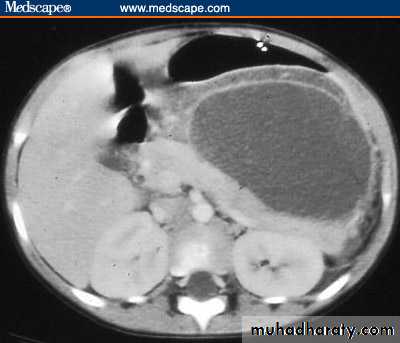

Acute Pancreatitis

CT used to

• 1. Pancreatic necrosis .• 2. An abscess.

• 3. Vascular complications.

• 4. Pseudocyst